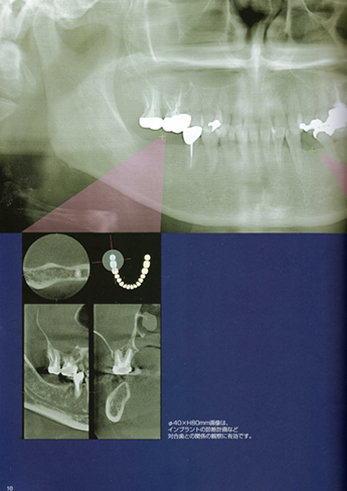

一般のレントゲンでは見えにくい部分も正確に診断できる歯科用CT

当院は歯科用CTを導入致しました。

- 医科用は最新でも0.5ミリ厚に対し0.1ミリまで設定でき

数ミリ単位での診断が要求される歯科では、

やはり歯科用CTが有利です。

また、医科用は面でしか捕らえることができず、

歯科においてより正確な判断ができませんでした。

画像が鮮明、立体画面でリアルに表現できます。

サイナスリフトに必要な骨の体積も計算出来ます。 - 骨の状態や血管の位置を正確に把握することで

治療の安全性が高まります。 - 事前確認が可能なため、切開部分が狭くなることで

患者さんの負担軽減につながります。

治療時間が短くなります。 - 事前に正確な情報を得られることが出来るので、

準備が容易になります。

経費の節減が治療費の減額にもつながるでしょう。 - 患者さんへの説明が容易になります。

患者さんにも分かりやすい画面になります。

フィルムや現像液を用いませんから、環境にも優しいです。

その他患者さんのメリットは計りしれません。